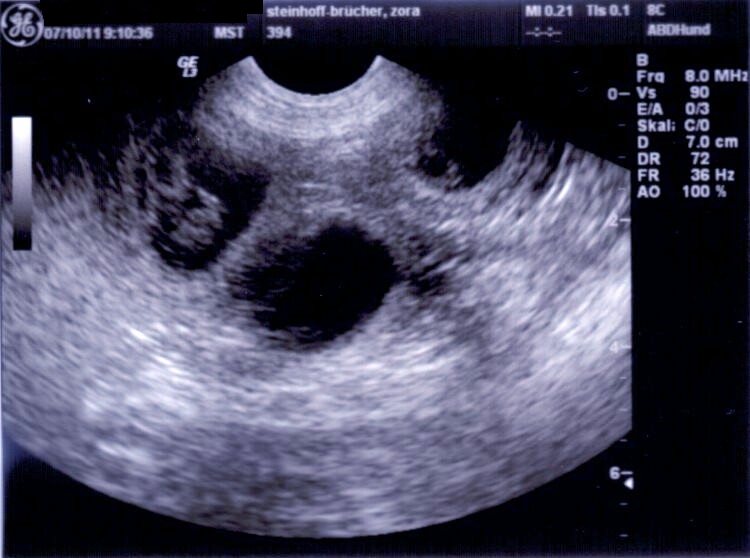

Hund Trächtigkeit Ultraschall

Hund Trächtigkeit Ultraschall. Woche durchgeführt.schon ab dem 23. Wir sollen am dienstag nochmal wiederkommen, weil es vielleicht noch zu früh war.

Ultraschall Bauchraum Kleintierpraxis am Uhlenhorst

Ultraschall Bauchraum Kleintierpraxis am Uhlenhorst from www.kleintierpraxis-uhlenhorst.de

Die aufnahmen zeigen ultraschalluntersuchung von unser hündin el shameera vom genfbachtal am 42.tag der trächtigkeit. Der ta konnte allerdings nur 2 früchte sehen. Viele grüße heike mit der werdenden mama xora

Die Untersuchung Auf Trächtigkeit Führen Wir Mit Dem Ultraschall Durch.

Theoretisch kann bereits ab dem 18. Um eine trächtigkeit bei der hündin eindeutig festzustellen ist eine trächtigkeitsuntersuchung beim tierarzt die sicherste vorgehensweise. Auf diese weise kann der mediziner bereits erahnen, wie groß der wurf wird, ob tatsächlich alle welpen leben und ob eventuell komplikationen bei der trächtigkeit vorliegen.